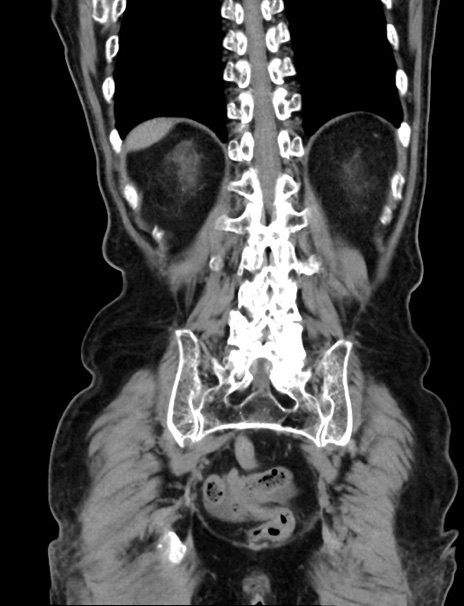

症例33(冠状断像)

【症例】70歳代 女性

【主訴】心窩部痛

【現病歴】延髄病変の精査・加療にて神経内科入院中。本日より心窩部痛あり。

【身体所見】右下腹部を中心に圧痛と反跳痛あり。

【データ】WBC 10900、CRP 0.02